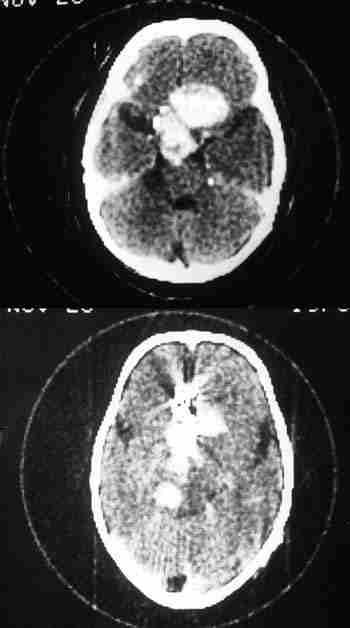

Figura 8. Las técnicas neurorradiológicas son fundamentales en la

cirugía de la órbita.